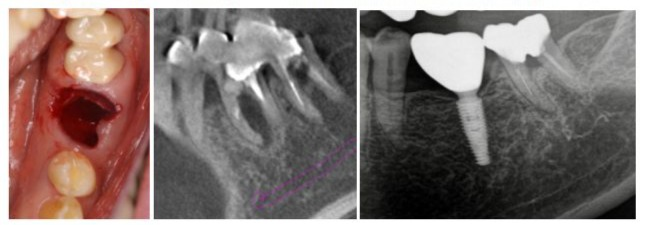

Treatment of Type E Sockets in the Mandible: Case 4 and 5.

In a type E socket, which does not allow implant stability with a WDI for the same reasons, there is neither septal bone nor any root socket, but buccal bone plate remains (Figure 3a). If the distance and bone quality to the mandibular canal or maxillary sinus allow insertion of an implant with possible high ITV, the implant can be inserted in the axial direction (Figure 3b,c).

Figures 3a to 3c: a. A case of healthy 72-year-old male patient retired who visited for tooth pain. A type E socket is apparent after tooth extraction; b. Mandibular molar without septal bone but existing axial bone tissue for implant stability with a sagittal tomographic image; c. A panoramic radiograph cut out after 4 years.

However, if insertion of the implant under that condition is not possible, the authors use tilted implants anchored to the lingual cortical plate of bone in the lower jaw and between the palatal cortical and lateral walls of the maxillary antrum cortical bone, avoiding maxillary sinus penetration (Figures 4a and 5a). One of the major concerns with the tilted implant procedure in the mandibular molar region can be perforation of the lingual cortical bone, possibly leading to serious hemorrhage [24,25]. Two important things must be done to prevent these complications. The first is precise preoperative diagnosis using CBCT with virtual implant simulation. The location of the implant platform is decided from the inferior alveolar nerve, both buccal and lingual bone crests, and the opposite tooth. Implant tilting, width, and length are also simulated based on the perforation point to the lingual cortical plate of bone at the same time (Figure 4b). The second is sufficient mucoperiosteal flap elevation in the surgery (Figure 4a). Elevation far beyond the expected perforation point is recommended for placing a mucosal dissector or saline-soaked gauze for soft tissue protection against the apex of preparation drills (Figure 4a). If these two things are appropriately done, it is the authors’ view that complications will never occur. The major advantage of this method is that it can achieve reliable initial stability with high ITV (more than 40 Ncm) [27,28]. When placing implants to cortical plate of bone with increased ITV of more than 40 Ncm, decreased or absent micromotion might help achieve predictable osseointegration [28]. This can lead to complete early final restoration, and, ultimately, the treatment period is shortened [28,29]. It has been reported that a definitive screw-retained prosthesis with zirconia was placed on standard and zygomatic implants for an edentulous maxilla seven days postoperatively [31]. Soft tissue of post-surgical healing around an implant appears to be completed after 2 weeks, and structural integrity is complete at the same time (about 2-3 weeks). Maturation of barrier function requires 6-8 weeks of healing [32]. This is based on the authors’ hypothesis that the goal is to improve barrier function by providing a highly biocompatible final prosthesis early on (2-3 weeks) and avoiding the need to attach and remove the implant abutments during soft tissue barrier maturation of 6-8 weeks post-surgically. After tooth extraction and immediate implant placement, the bone undergoes significant modeling in the edentulous ridge of the alveolar process, resulting in a decrease of the ridge dimension [19]. Moreover, when a flap procedure has been added, bone modeling might be accelerated. Regarding to the space distance between an implant and the adjustment bone wall, if the space is >2 mm, the site ought to be grafted with primary closure. In contrast, even if the space is >2 mm, success of the implant may be attained with no primary closure, no grafting, and no flap elevation [4]. In type D and E sockets, flap elevation might be required; thus, aggressive SPT is recommended if the gap is ≥3